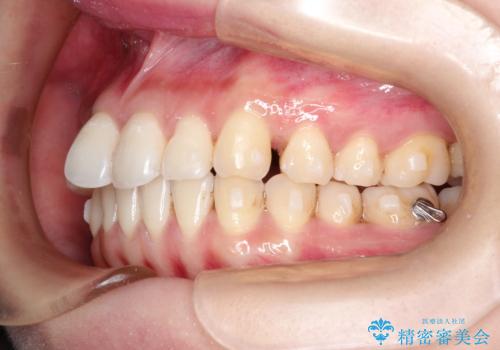

初診時の歯並びの状態としては、上下にガタガタがある状態であり、特に上の前歯(左上1番)の捻じれを最も気にしていらっしゃいました。

口元の位置も悪くなくスペース必要量も軽度であったため、非抜歯/マウスピース矯正にて治療を行いました。

前歯の捻じれを改善するためにスペースを作る必要があり、前歯の歯の間を削って簡単に直す方法もありますが、奥歯のズレが認められたため、大臼歯後方のスペースを利用し、根本的な原因からしっかりと治療を行いました。